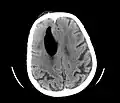

| Pneumocephalus and comminuted fracture of the frontal sinus |

CT scans of patients with a tension pneumocephalus typically show air that compresses the frontal lobes of the brain, which results in a tented appearance of the brain in the skull known as the Mount Fuji sign.[1][2][3] The name is derived from the resemblance of the brain to Mount Fuji in Japan, a volcano known for its symmetrical cone. In typical cases, there is a symmetrical depression near the midline (such as the crater of a volcano), due to intact bridging veins.[3] Its occurrence seems to be limited to tension pneumocephalus (not occurring in pneumocephalus without tension).[4] The sign was first described by a team of Japanese neurosurgeons.[5]